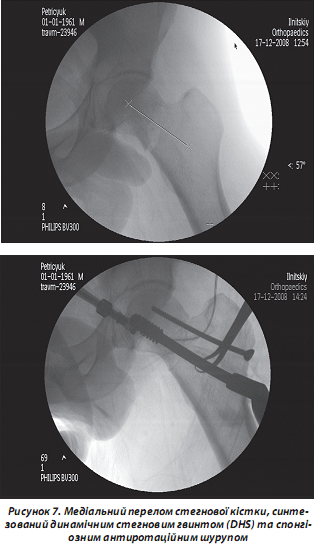

Фіксуючи шийку стегнової кістки, гвинт протягом усього періоду консолідації забезпечує динамічну компресію лінії перелому. Це відбувається завдяки особливості гвинта: він ковзає в трубці екстрамедулярної накісткової частини фіксатора, розміщеного на зовнішній поверхні стегнової кістки. Інколи пластина може бути підсилена пластиною Regazzoni, яка підтримує вертлюг. При використанні фіксатора DHS при медіальних переломах слід увести в шийку стегнової кістки спонгіозний антиротаційний шуруп паралельно шийковому гвинту, що запобігає ротації головки при його вкручуванні (рис. 7).